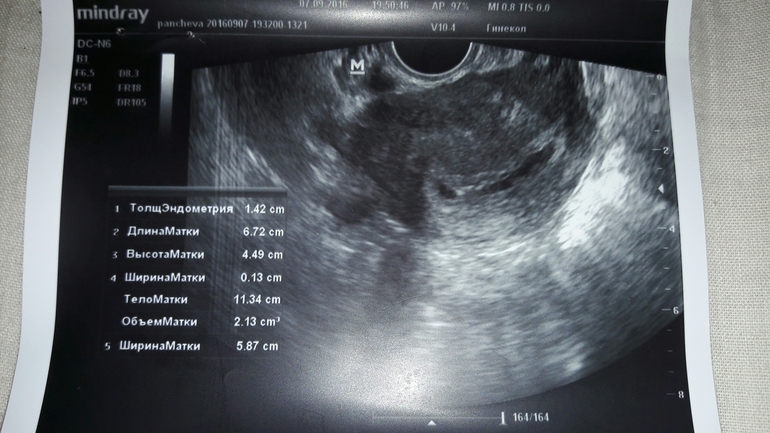

Результаты: УЗИ, КТГ, доплера, скринингаНас нашли пя 7 мм. Жт 15 мм. Киста есть с кровотоком аж 5*4 см. Так же нечто( ни кто не знает что это) возможно из-за этого кровит. Срок 4 недели и 2 дня( это эмбриональный?) А вот и нечто с права вытянутое.